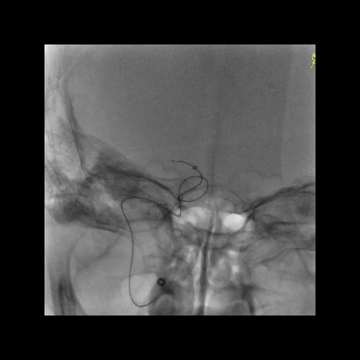

持续负压下回收中间管,后造影示颈内动脉后交通位置闭塞,提示血栓较大且坚硬,从5F中间管头端脱落。

血栓坚硬,微导丝最终成袢通过闭塞位置,微导管跟进进入M1,释放支架。